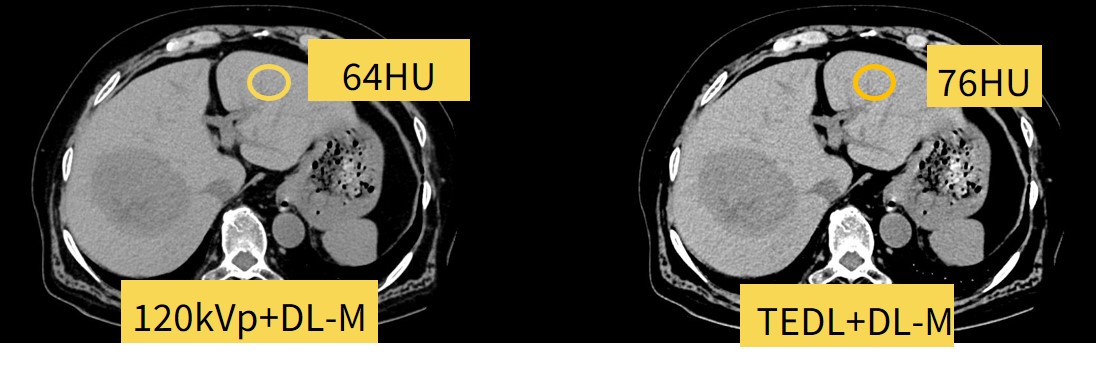

中等度腎機能障害症例があり造影剤量を従来の7割にして撮影した症例になります。

120kVpと比較してTEDLではよりコントラストのついた画像になっており、肝実質と門脈のCT値を計測するとTEDLのほうがCT値の差が大きいことが確認できます。

撮影時に低管電圧にする設定の手間が不要で同等の画像を得ることが可能でした。

Fig6. 造影剤低減撮影でも、TEDLを使用することで撮影時の管電圧切り替えが不要